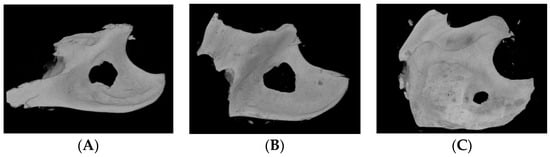

Three-dimensional images of the mandibular specimen were reconstructed from the specimen μ-CT images (Figure 3). A round defect in the mandibular angle area was occupied by new bone, and new bone regeneration was observed. A round defect trace was observed, and new bone was generated from the surrounding defect. Shallow and thin new bones were observed, which were more prominent in the older age groups. The space not occupied by new bone was larger in the 2 M group than in the other groups (Figure 3A). In contrast, the bone defect in the 20 M group was almost completely occupied by new bone, and only a small round gap remained (Figure 3C).

Figure 3. Three-dimensional (3D) reconstruction image of micro-computed tomography (μ-CT) of the mandible bone of (A) 2 M, (B) 10 M, and (C) 20 M groups. The new bone regeneration was more prominent in the 20 M group.